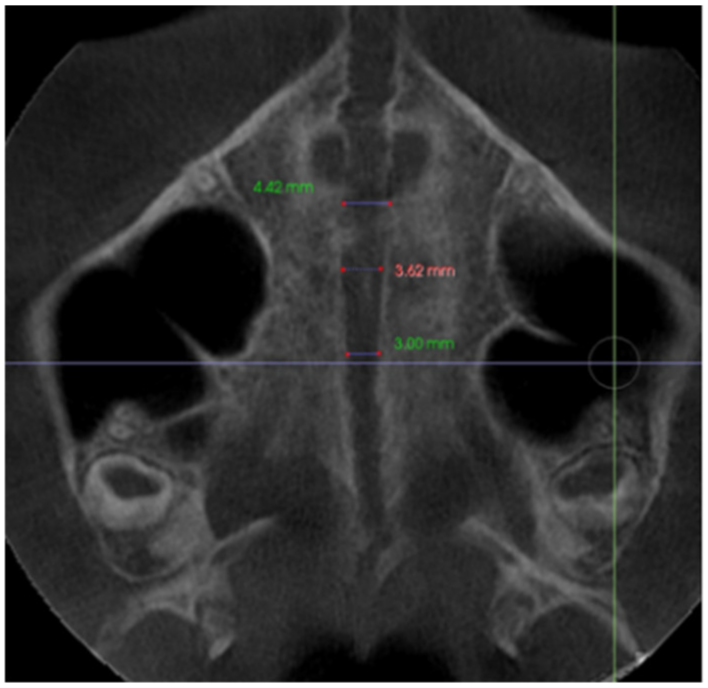

| Sutural expansion (SEM) | The sutural expansion in the middle of the palate. Distance between the left and right external border of the palatal aspect of the maxilla, in the middle of the palate between the palatine bone and the nasal floor, on a coronal cross-sectional slice at first molar. Through the midportion of the first molar. | ![]() |